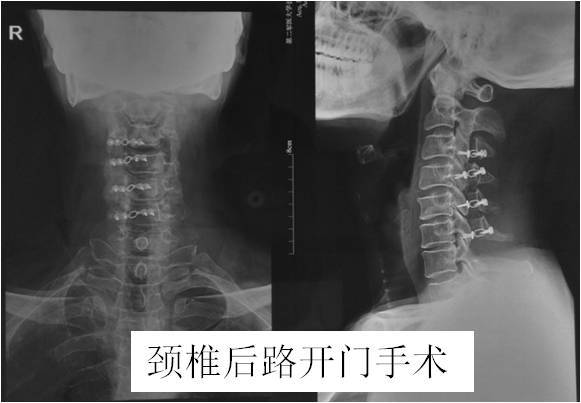

对于少数压迫节段很多,有椎管严重狭窄的脊髓型颈椎病,需要从脖子后面开刀(颈椎后入路),如颈后路椎管成形术(图10),椎板切除术。这种手术方式的特点:手术减压范围大,但需要剃光头,手术创伤相对较大,切口大约10cm,术后2—3天可戴颈托下地。